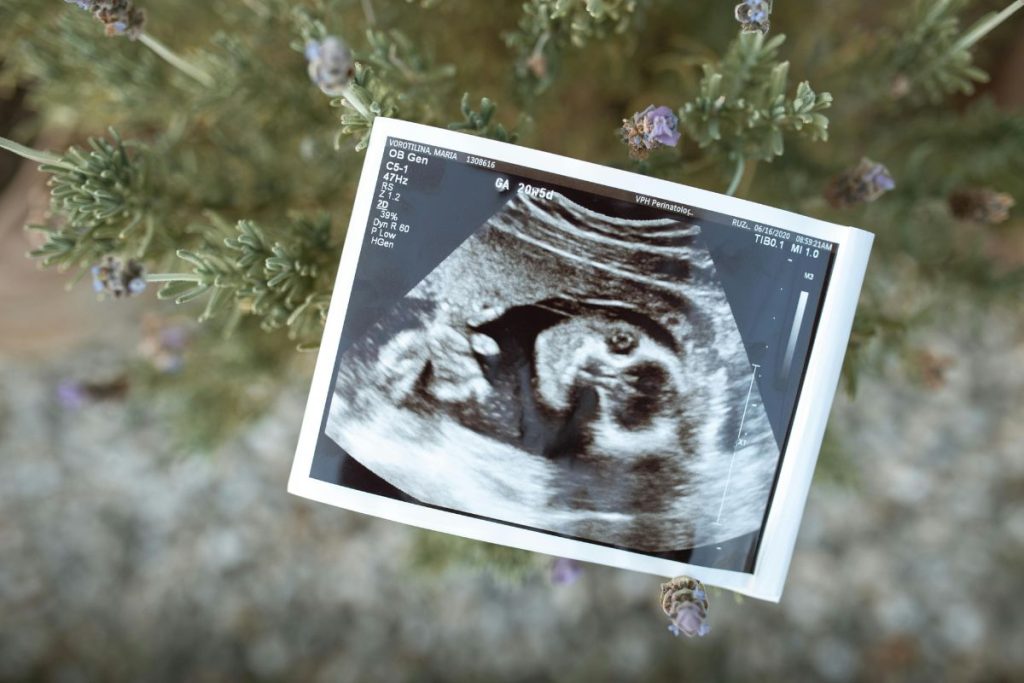

The Role of Genetic Screening

One of the most important breakthroughs in reproductive medicine is the genetic testing of embryos. PGT helps identify embryos with the correct number of chromosomes (euploid embryos). Chromosomal abnormalities are a leading cause of failed implantation and miscarriage. By transferring genetically normal embryos, intended parents can dramatically increase the likelihood of pregnancy and reduce the risk of genetic disorders.

Genetic screening is especially valuable for:

- women over 35 years old, as egg quality naturally declines with age;

- couples with a history of recurrent pregnancy loss;

- parents with known genetic conditions.

This careful selection ensures that the embryo not only looks healthy but also has the necessary genetic stability to develop into a healthy pregnancy.